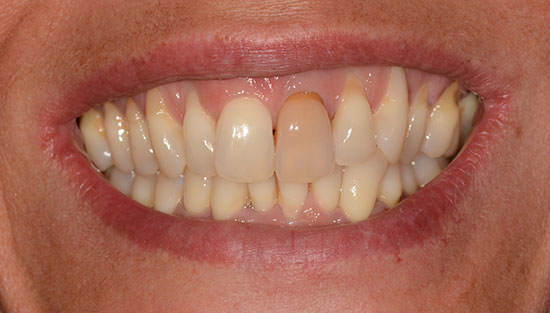

Cas 4 : 1 incisive centrale - 2 séances de 60 minutes la même journée

Une facette en céramique ne peut masquer intégralement une dent très teintée (ici orangée)